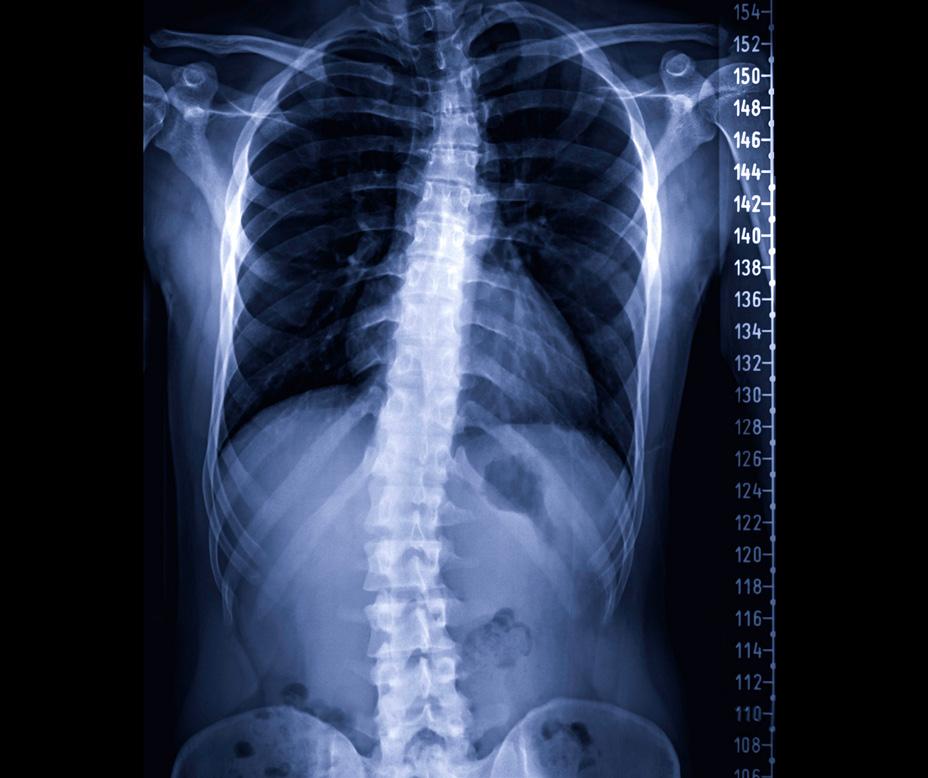

Figure 1. Preoperative and postoperative (PO) radiographic evaluation of adult spinal deformity with T4-L1-hip axis planning. (A) Standing anteroposterior and lateral scoliosis radiographs demonstrating preoperative and postoperative coronal alignment. The preoperative image reveals adult idiopathic scoliosis (Lenke 6) with a lumbar curve of 75° and main thoracic curve of 50°. The postoperative anteroposterior radiograph demonstrates correction following posterior spinal instrumented fusion from T4 to pelvis. (B) Lateral scoliosis radiographs of preoperative, planning, and postoperative radiographs with corresponding T4-L1-hip axis parameters. The patient’s pelvic incidence (PI) of 40° establishes a target L1-pelvic angle (L1PA) of −1° based on the equation L1PA = PI × 0.5 − 21°. Preoperatively, the patient demonstrated L1PA of 2°, T4PA of 19°, and C2PA of 24°, indicating marked thoracolumbar kyphosis. The surgical plan targeted restoration of L1PA to −3°, T4PA to 3°, and C2PA to 7°, maintaining T4-L1PA mismatch within the optimal range of −3° to +1°. Postoperative radiographs confirm achievement of planned alignment with L1PA of −3°, T4PA of 3.5°, and C2PA of 10.5°. The T4-L1PA mismatch of +17° was preoperatively reduced to +6.5° postoperatively.